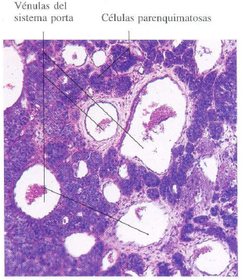

Sección horizontal de la parte tuberal de

la hipófisis. Se observan numerosas vénulas del sistema porta hipofisario seccionadas transversalmente.

Entre ellas se encuentran las células que constituyen el parénquima de esta porción de la glándula.